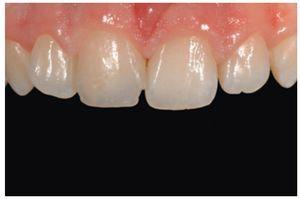

Figura 49 Vista de las restauraciones y los elementos rehidratados después de 72 horas.

Figura 50 Buena integración estética de las restauraciones y salud de los tejidos periodontales 30 días después del tratamiento.